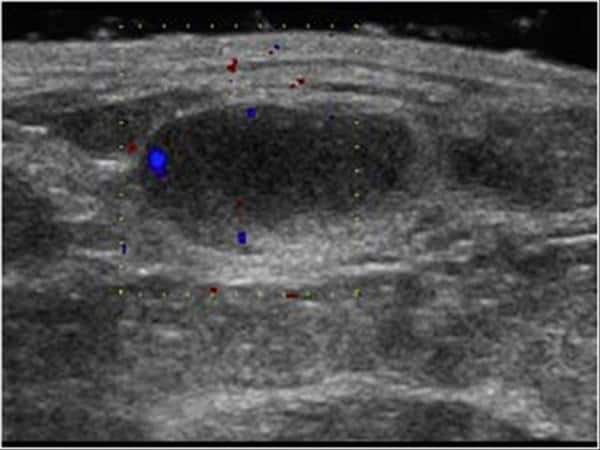

Hoại tử mỡ tuyến vú - Ảnh 4

Hoại tử mỡ tuyến vú

» Thông tin: Nữ giới – 54 tuổi.

» Lâm sàng: Khối tuyến vú / Sau phẫu thuật u vú.